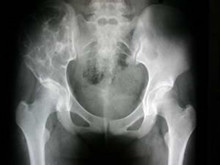

小儿动脉瘤样骨囊肿

动脉瘤样骨囊肿是一种良性单发骨肿瘤,具有均匀的泡沫透明区域。这种疾病经常发生在大...

X线平片、活体组织病理检查(活检)